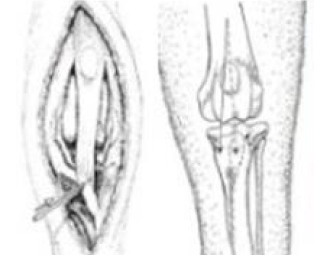

활차구 성형술

대퇴근막 중첩술

경골결절 변위술

경골회전방지&자봉합

슬개골 탈구 수술과정